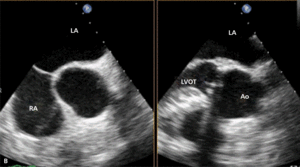

Rycina 4. Wynik przezskórnego leczenia defektu Gerbode w trójwymiarowej echokardiografii przezprzełykowej [A], w 64-rzędowej tomografii komputerowej [B].

Leczenie zabiegowe nabytej wady typu Gerbode to przede wszystkim ponowny zabieg kardiochirurgiczny. Szacowana na podstawie danych sprzed kilkudziesięciu lat śmiertelność okołozabiegowa wynosi około 16% [25]. Gdy nie ma aktywnego zapalenia wsierdzia i przy współistnieniu korzystnych warunków anatomicznych możliwe jest również przezskórne zamknięcie ubytku. Zastosowanie znalazły tutaj zapinki do mięśniowego VSD [30], ubytku w przegrodzie międzyprzedsionkowej (atrial septal defect, ASD) [31] czy PDA [32]. W ośrodku autorów do zamknięcia tego typu ubytku u chorego po AVR (zastawka Sorin Pericarbon) użyto zatyczki dedykowanej do okołobłoniastego VSD (perimembranous VSC, pmVSD), uzyskując pełne zamknięcie ubytku (ryc. 3, 4). Podobnie jak w przypadku innych implantacji zatyczek w okolicę mechanicznej zastawki serca, podstawowym problemem jest taki dobór urządzenia, aby zminimalizować prawdopodobieństwo zablokowania dysków zastawki przy jednocześnie możliwie całkowitym wypełnieniu ubytku.